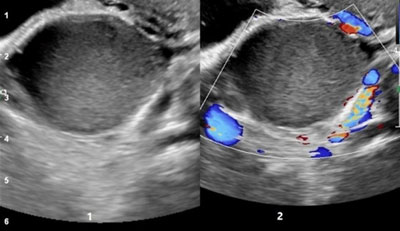

• Ultrasound Imaging: Useful for detecting ovarian endometriomas (chocolate cysts) and other visible abnormalities.